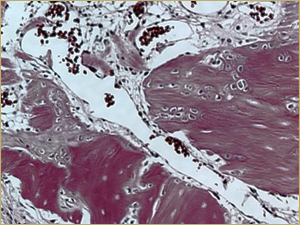

After 2 weeks, grafted mature cortical bone fragments were present in the rabbit maxillary sinuses augmented with autogenous bone grafts (Fig. 3a). Few lacunae within the grafted bone were occupied by osteocytes (Fig. 3b). The margins of the grafted particles demonstrated active bone turnover and remodelling. Resorption of the grafted mature cortical bone was coupled with areas of newly formed woven bone. The new bony regenerate demonstrated plump osteocytes and osteoblasts.

Figure 3b: High-power histologic examination of rabbit maxillary sinus augmented with autogenous bone graft at 2 weeks after grafting. H&E stain, 200× magnification.